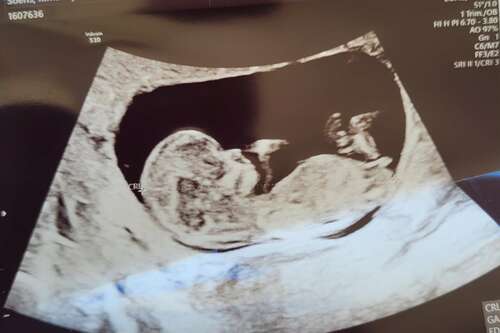

Lastige week, donderdag mag ik om de eerste echo van ons nieuwe kleintje, zal dan zo goed als 13 weken zijn. Komende Vrijdag is het n jaar geleden dat ons dochter aan 40w is gestorven en zaterdag is het dan haar eerste verjaardag.